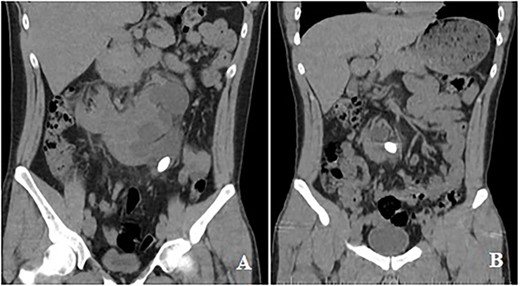

A 24-year-old male patient presented with a complaint of left flank pain. The patient complained of intermittent pain for 5 years and had no prior history of kidney stones or hematuria. As shown in Fig. 1(A and B), during the non-contrast computed tomography (CT) scan of the entire abdomen conducted 5 months ago, a horseshoe kidney anomaly was detected in the patient. At the same time, a 22-mm stone localized to the collecting system at the level of the kidneys with fusion in front of the aorta and a 6-mm stone located in the middle part of the left kidney were found. Subsequent evaluation revealed that the stone had moved and settled in the left renal pelvis. Due to the renal anomaly, any leftover fragments following RIRS will not spontaneously fall out because the stone is mobile between the lower calyx and the renal pelvis. Therefore, a combined laparoscopic pyelolithotomy with RIRS was planned.